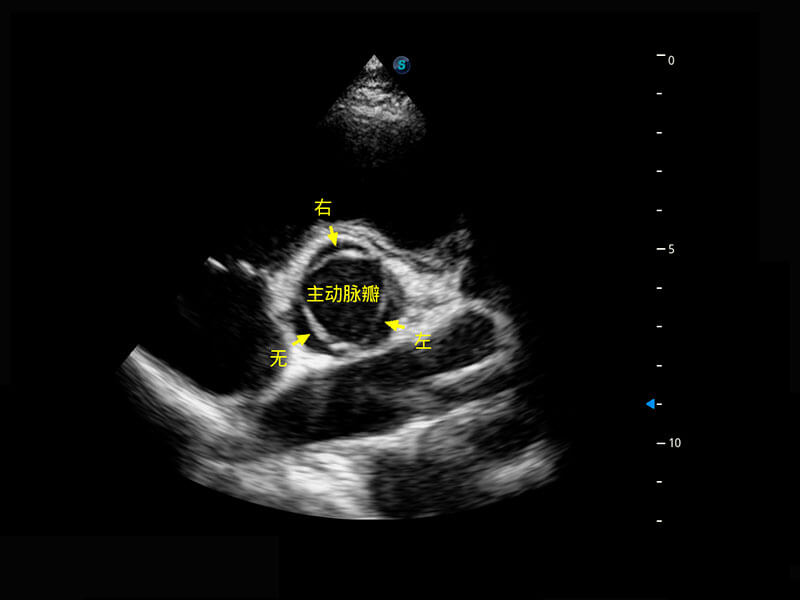

生殖健康

P60优异的图像质量搭载专科探头,在妇科基础疾病的诊断、卵泡生长的监测、输卵管通畅情况的判别等方面为您提供生殖应用方案。